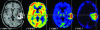

Imaging in patients with brain tumors aims toward the determination of the localization, extend, type, and malignancy of the tumor. Imaging is being used for primary diagnosis, planning of treatment including placement of stereotaxic biopsy, resection, radiation, guided application of experimental therapeutics, and delineation of tumor from functionally important neuronal tissue. After treatment, imaging is being used to quantify the treatment response and the extent of residual tumor. At follow-up, imaging helps to determine tumor progression and to differentiate recurrent tumor growth from treatment-induced tissue changes, such as radiation necrosis. A variety of complementary imaging methods are currently being used to obtain all the information necessary to achieve the above mentioned goals. Computed tomography and magnetic resonance imaging (MRI) reveal mostly anatomical information on the tumor, whereas magnetic resonance spectroscopy and positron emission tomography (PET) give important information on the metabolic state and molecular events within the tumor. Functional MRI and functional PET, in combination with electrophysiological methods like transcranial magnetic stimulation, are being used to delineate functionally important neuronal tissue, which has to be preserved from treatment-induced damage, as well as to gather information on tumor-induced brain plasticity. In addition, optical imaging devices have been implemented in the past few years for the development of new therapeutics, especially in experimental glioma models. In summary, imaging in patients with brain tumors plays a central role in the management of the disease and in the development of improved imaging-guided therapies.